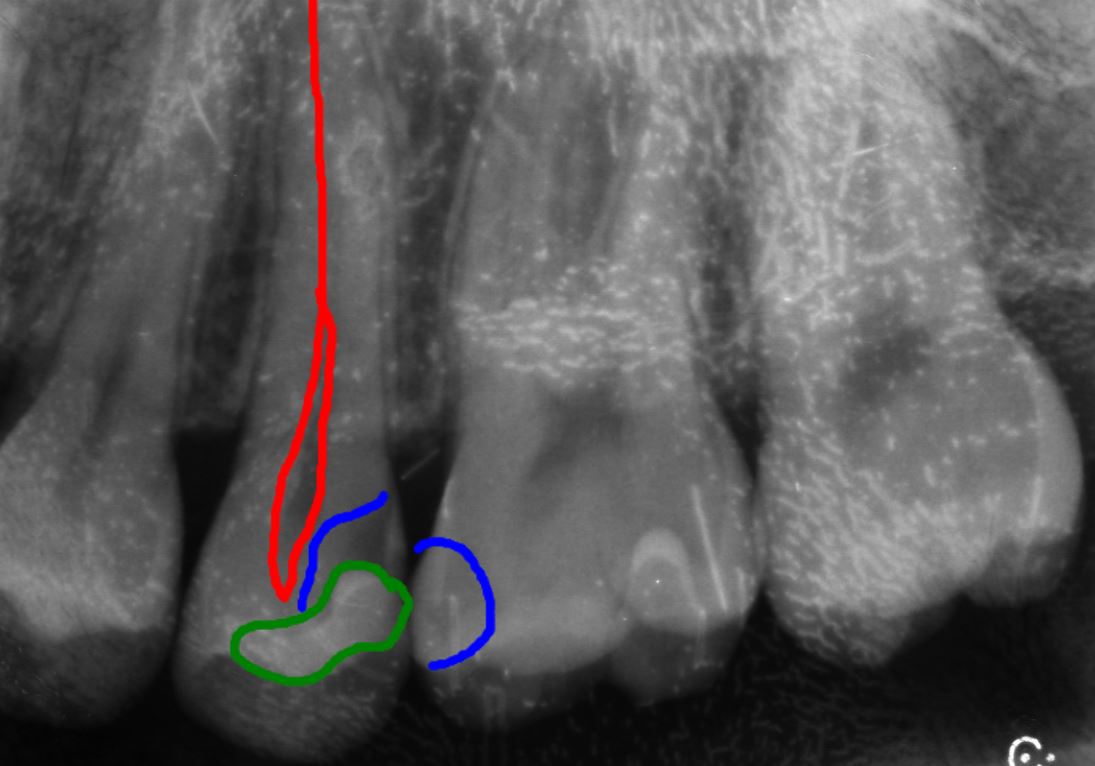

40代男性 上顎第二小臼歯が2次カリエス

口腔内/レントゲン画像

下の部分的なレントゲンになります。

青い部分が虫歯になり、赤色の歯の神経との距離がかなり近くもしくは虫歯で感染が起きている場合があります。痛みなどの症状がなかったため、MTAセメントを使用し神経保護を行なっていきます。